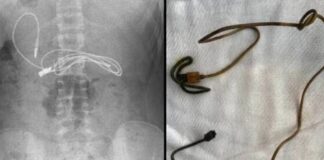

Είχε έντονους πόνους στο στομάχι και όταν πήγε στο γιατρό βρήκαν...